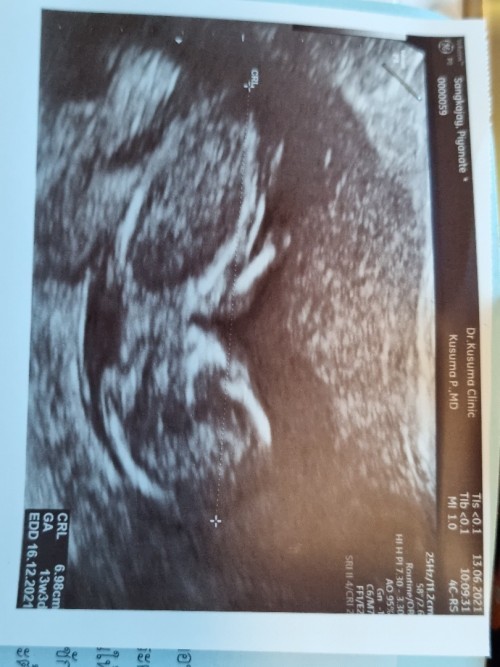

รูปซาวด์เด็กน้อย 3 เดือน

12w+4 ยังไม่เห็นเพศเลยค่ะ ใครดูออกมองให้เค้าหน่อย หมอ ไม่ยอมบอก ขอดูรูปซาวด์เด็กๆ3เดือนหน่อยค่ะ อยากเห็นๆ #ขอบคุณล่วงหน้านะคะ

13วีค3วัน หมอยังไม่ดูเพศให้เลยคะ